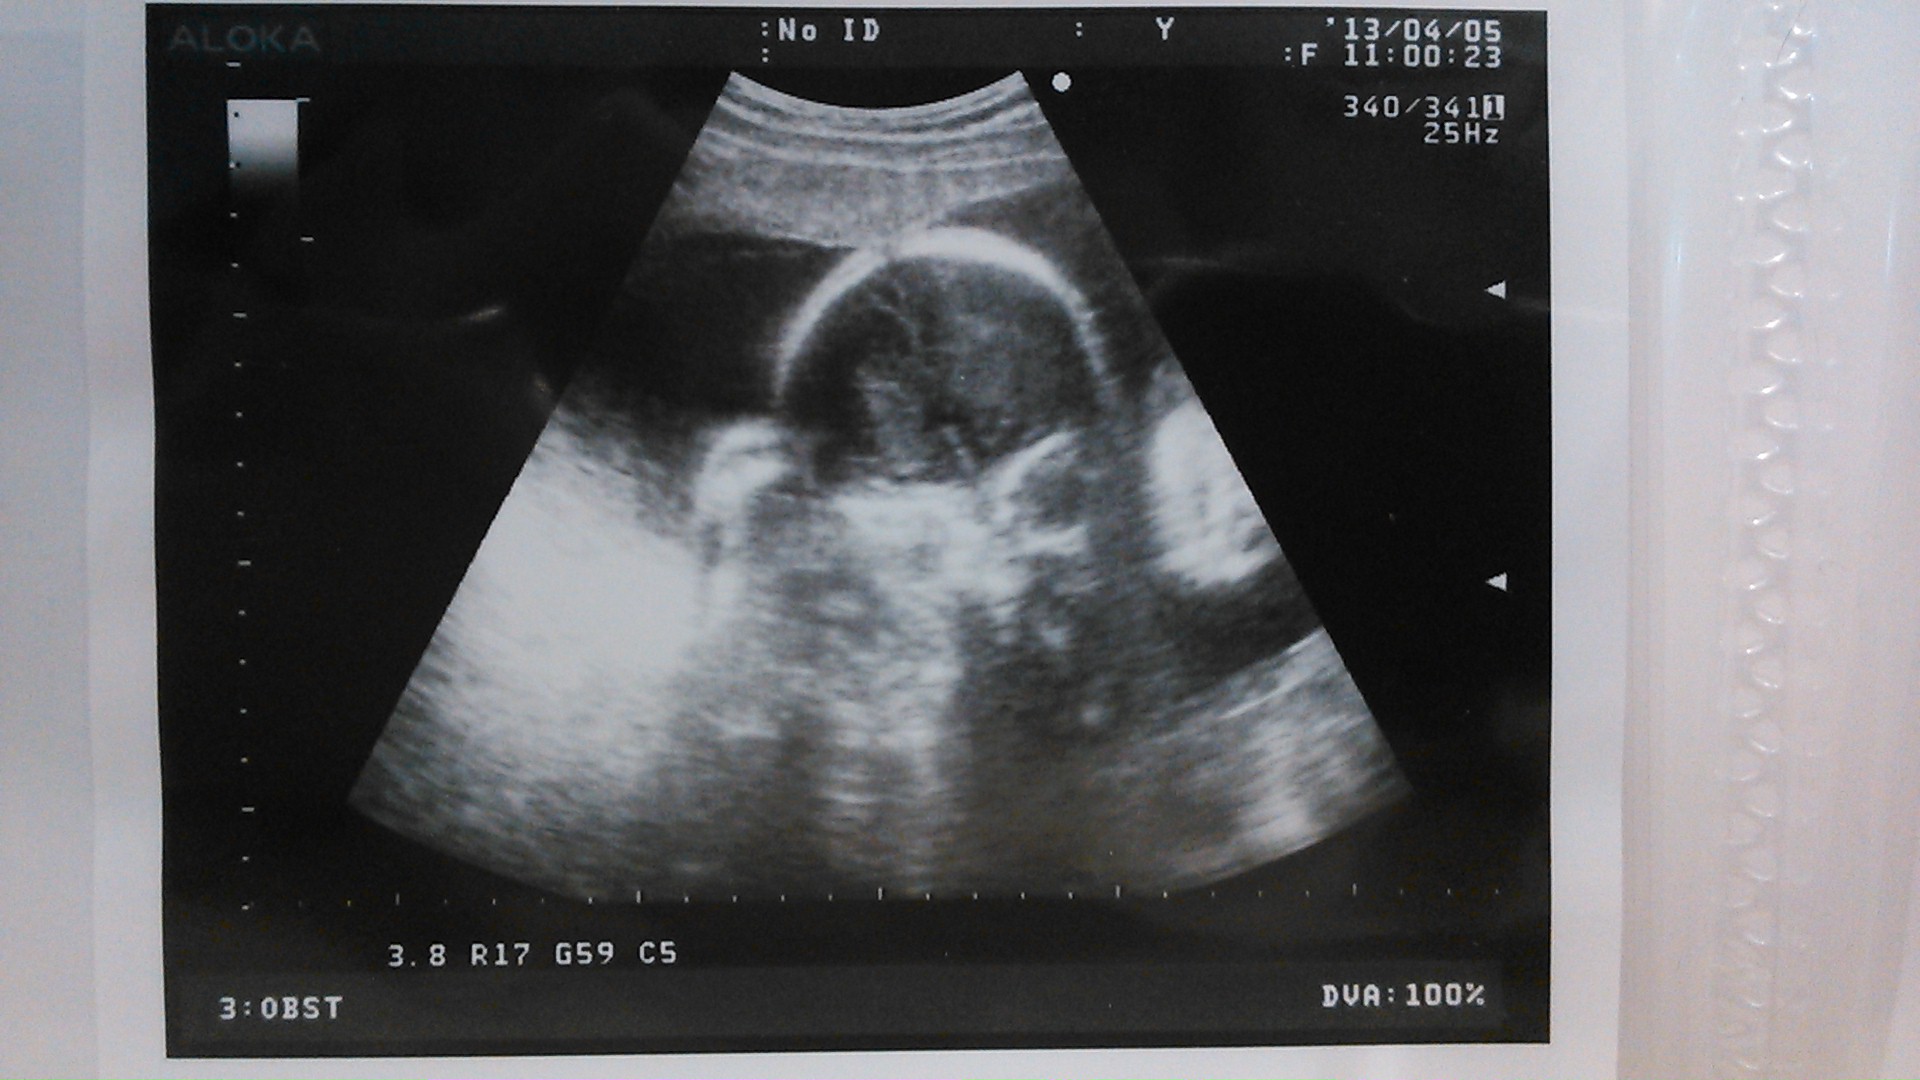

echo